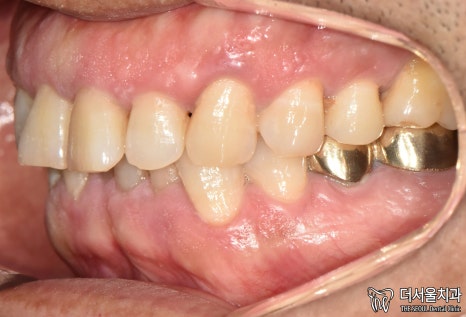

5. 완료

현충일 공휴일 정상진료

최종 완료된 모습입니다.

첫 진료 때보다 깔끔해졌죠?

치아와 비슷한 색으로 된

‘지르코니아’ 크라운을 씌워드렸는데요.

튼튼하다는 특징도 있어

많은 분께 선호되고 있는 재료입니다.

실제로 보면 이렇게

다른 치아와 크게 다르다는 점이 없죠?

환자분도 치료 결과에 만족스러워 하셨습니다.

엑스레이로 한번 더 체크했을 때도

뼈와 잘 붙었습니다.